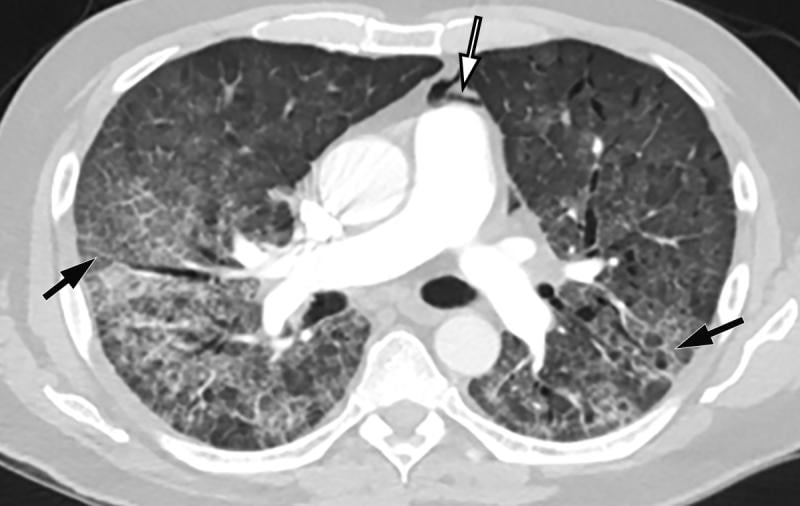

This photo gallery shows the variety of radiological presentations of COVID-19 (SARS-CoV-2) in medical imaging, including computed tomography (CT), radiograph X-rays, ultrasound, echocardiograms and magnetic resonance imaging (MRI). The radiology images show examples of typical COVID pneumonia in the lungs and the numerous complications the virus causes in the body in multiple organs, including the brain, kidneys, heart, abdomen and vascular system.

Ultrasound, especially hand-held ultrasound imaging devices, have become a primary imaging modality for novel coronavirus because of the ease to bag the device and sterilize it after use. CT and mobile X-ray systems are also used as front-line imaging systems for COVID-positive or suspected COVID patients.